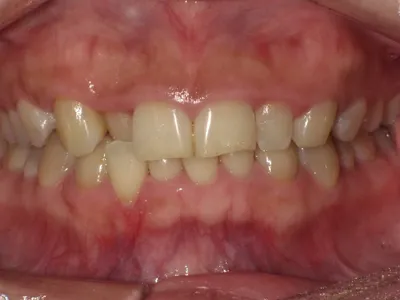

症例1

before

after

| 主訴 | ガミースマイルを治したい |

|---|---|

| 治療内容 | 矯正,歯槽骨整形術,歯肉切除術,ラミネートベニア |

| 治療期間 | 2年 |

| 費用 | 990,000円(税込) |

| リスク・副作用 | 矯正により治療期間中染みたり、咬合痛が出てしまうことがあります |